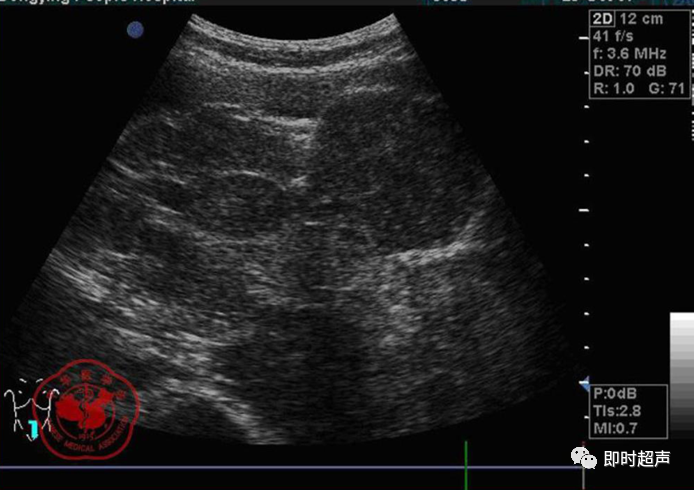

• GIST的发病机制与KIT信号通路的激活有关。• KIT是一种酪胺酸激酶跨膜受体蛋白,未经“装配”过的KIT蛋白是一种非活化的单体,参与细胞膜形成。几乎所有GIST都表达了KIT蛋白,而且大多突变的KIT基因保留了表达KIT蛋白的特性。c-kit内的突变主要见于恶性病例,特别是外显子11的点突变,还有外显子9、13和17,可以导致本质的或配体独立的c-kit激活,引发细胞的无序增殖和凋亡。这些具有功能的突变是GIST发病机理的关键,并且与肿瘤的恶性程度和预后较差相关。• GIST约75%发生于50岁以上老年人,中位年龄为58岁,无明显差异。• 可以发生在消化道从食道到肛门的任何部位,偶尔可原发于网膜、肠系膜和腹膜后,约50%发生在胃,25%发生在小肠,不足10%发生于食管、结肠及直肠。大体观察:肿块多境界清楚,类圆形,结节状,部分有假包膜。切面灰白、灰红,质韧,部分质嫩呈鱼肉状,伴有出血、坏死、囊性变。• 肿瘤组织主要由两种细胞组成,一种为长梭形细胞,细胞质丰富,嗜酸性,细胞核呈梭形或杆状;另一种为上皮样圆形或多角形细胞,细胞肥胖,胞质少。两种瘤细胞常呈束状、编织状或旋涡状排列。• 部分病例细胞异型明显,核分裂象增多,可见病理性核分裂象和瘤巨细胞。梭形细胞界不清楚,胞质丰富,淡染,轻度嗜伊红或略嗜碱,可有纤细、长梭形、短梭形或胖梭形、卵圆形,可见核仁。细胞核两端钝圆,部分病例胞质呈空泡状,位于核一端形成核端空泡胞,多呈交叉束状、旋涡状、席纹状及栅栏状排列。上皮样细胞胞浆丰富或透亮,多呈弥漫片状、束状或巢状排列。肿瘤间质可有出血、囊性变、坏死及黏液变,可见炎性细胞浸润。CD34抗原是一种115kd的糖基化蛋白,50%~80% GIST的CD34表达为阳性,CD34对鉴别GIST和典型的平滑肌瘤,神经鞘瘤还是非常有用的标记物,因后两者的CD34一般是阴性的。但CD34在诊断GIST上其特异性受到限制,一般情况下CD34多与CD117联合应用,方能提高GIST的诊断率。• 与肿瘤大小、发生部位、肿物与肠壁的关系以及肿瘤的良恶性有关。• 肿瘤较小者(直径小于2cm)常无症状,往往在体检和其它手术时无意中发现。• 肿瘤发生于胃肠道腔内时大多表现为呕吐、腹痛及消化道出血,而发生于胃肠道腔外的则主要表现为腹部包块。• 最常见的临床症状是中上腹部不适、腹部肿块及便血。• 对于临床发现的消化道(包括肠系膜、网膜、后腹膜)实体肿瘤,在排除其他常见肿瘤后,才考虑GIST。目前,诊断GIST有三条标准:③肿瘤组织具有梭形细胞和上皮样细胞两种基本细胞成分的病理学特征。这是诊断GIST金标准。CD117阳性者或CD117阴性而CD34阳性者,且伴平滑肌和神经双向分化或无分化者,可诊断为GISTs;以Desmin和SMA强阳性,而CD117阴性诊断为平滑肌肿瘤;以S-100阳性,CD117、Desmin、SMA均阴性诊断为神经鞘瘤。• GISTs的分型与组织学良恶性的关系:研究证实GISTs非单一分化的肿瘤,具有多向分化。• 当前GISTs的良性、交界性和恶性判断标准多参照Amin等提出的标准:②交界性:核分裂<5/50HPF,但肿瘤>5cm;• 另外研究显示,平滑肌型大多数为良性,少数为交界性和恶性,神经源型为恶性,双向分化亚型和未分化型为交界性和恶性,提示GISTs的分化型与其良恶性之间有一定关系。• 胃间质瘤早期多局部侵犯,后期出现肝转移和腹腔内种植,小肠间质瘤早期即可出现转移• 主要有超声扫描(检出率30%左右)、纤维内镜、超声内镜、CT、MRI、普通X• 线检查(胃肠钡餐造影、小肠插管气钡双重造影)、选择性血管造影检查等。• 不同部位的GIST,各种检查方法的敏感性不同。以CT检查为佳,尤其是螺旋CT,分辨率最高,可以三维重建,直接显示肿瘤大小、形态、密度、内部结构、边界,对邻近组织的侵犯也看得很清楚,同时还可观察其他部位的转移灶,有利于分期、鉴别与诊断。• MRI具有多轴成像及反映肿瘤内部成分的优点,尤其是动态扫描及各种新的扫描系列的出现更使其可以普及应用。• DSA检查对于GIST,特别是有消化道出血的患者更有价值。• 上述影像学检查表现并非特异性,与胃肠道平滑肌肿瘤、神经源性肿瘤鉴别困难。明确诊断要依赖病理免疫组化等手段。• 超声图像特征 肿物体积较小者(直径< 5. 0 cm )多为实性病变, 呈类圆形, 边界清晰, 内部回声多为较均匀的低回声。• 肿物体积较大者(直径> 5. 0 cm ) 多为混合性病变,呈不规则圆形或分叶状, 多数边界尚清晰, 以实性为主的病变内部为不均质中低回声伴不规则液性区及斑点状强回声; 以囊性为主的病变囊壁较厚,有分隔, 部分囊腔内可见点状、团状低回声。CDFI显示肿物实质回声内血流均较丰富。病例1:患者男, 62岁。自扪腹部包块2月余,包块增大20天就诊。查体:腹部平坦,无腹壁静脉曲张,无胃肠型及蠕动波,腹肌软,剑突下5cm处及左肋缘下可触及一质韧包块,大小约15*12cm,活动度差,边界尚清,包块深压痛,全腹无反跳痛。化验检查AFP:3.66(1.09-8.04)ng/ml,CEA:2.85(0-5)ng/ml。体格检查:一般情况良好,全腹软、平坦,腹部无压痛。超声检查:患者仰卧位时左上腹于胰尾前方可见一大小约6. 1 cm ×5. 8 cm ×5. 3 cm实性均质低回声,形态规则,包膜完整,边界清晰,活动度大;右侧卧时,肿块移至胰头右前方(图1) ;于其内探及丰富血流信号。体格检查:一般情况良好,腹丰满,上腹部有轻压痛,未扪及明显肿块。超声检查:患者仰卧位时左上腹于胰尾前方、脾门处可见一大小约10. 0 cm×8. 8 cm×7. 6 cm 实性低回声(图2) ,形态规则,包膜完整,边界清晰,肿块活动度大;右侧卧时,肿块移至左肝下间隙,回声尚均质;于其内探及较丰富血流信号(图3) 。图3 腹腔低回声肿块位于左肝下间隙,于低回声肿块内探及较丰富血流信号向壁外生长的胃肠道间质瘤, st为胃腔,箭头所指为胃壁, T为向外生的肿瘤• 胃间质瘤的定位准确率要高于十二指肠及小肠间质瘤,这主要是因为胃的解剖位置相对固定,且通过饮水使胃腔充盈,可清晰的显示胃壁的各层结构及肿块与胃壁的关系。肿块多表现为粘膜下、肌层或浆膜下低至中等回声团块,可向腔内、腔外或腔内外生长。但当肿瘤较大或浸润周围脏器时,超声定位仍有困难, 因此,超声如发现上腹部肿块且怀疑来源于胃者,应尽可能嘱其饮水充盈胃腔,并多角度、多切面观察肿块与周围脏器的关系,以提高定位的准确性。• 十二指肠间质瘤的定位亦较准确,但降部的外生性肿块常与胰头粘连而误诊为胰腺肿瘤回声均匀且位置较深的间质瘤亦可能误为胰头周围淋巴结。• 空、回肠间质瘤常因肿块较大,多发,位置不固定而难以定位,往往误诊为腹、盆腔或腹膜后肿瘤,超声检查如发现肿块局部肠壁增厚,肿块与肠道随呼吸同步运动时可作出定位诊断。• GIST的声像图表现有助于其良、恶性的鉴别:良性肿瘤多体积较小,圆形或椭圆形,回声均匀,边界清晰。恶性肿瘤多较大,呈不规则分叶状,回声不均匀,内部易出血、坏死、囊变。• 肿瘤长径与肿瘤内部是否出现无回声区在良、恶性病变之间的差异有统计学意义,是判断良恶性的有效征象。• 如以肿瘤长径>5cm为诊断恶性标准,其敏感性、特异性及准确性均较理想。超声可为临床提供胃肠道间质瘤的部位、大小、边界、回声等较多有用信息,一部分病例可作出定位、定性诊断,并可在术后或复发患者药物治疗期间对其进行动态观察;CDFI方便快捷、无需造影剂即可对间质瘤周边及内部血流进行观察,可为临床医师提供肿瘤血供情况。但未发现腹腔或肝脏转移时,超声判断胃肠道间质瘤性质有一定难度。• 目前临床上对GISTs的治疗效果并不十分满意。治疗仍以手术为主,对无法手术切除或已有转移的GISTs患者进行甲磺酸伊马替尼化疗。• 手术方式取决于肿瘤大小、部位和术中冰冻切片结果等。• 发生在胃的间质瘤,可首选胃大部切除术;发生在十二指肠的间质瘤可行保留胰头的十二指肠切除术或胰十二指肠切除术;发生在小肠的间质瘤可行肿瘤肠段切除术;发生于结肠的间质瘤可行左半或右半结肠切除术;发生于直肠的间质瘤可行肿瘤局部切除术。一般情况下无需淋巴结清扫。• 术后随访监测,复发者单个病灶可考虑手术切除;多发或转移特征者应试行甲磺酸伊马替尼化疗,并监测肿瘤大小及数目的改变。• 随着分子靶点药物进入肿瘤临床,一种小分子化合物———酪胺酸激酶受体抑制剂,美国称为Gleevec,欧洲叫做Glivec(格列卫),在治疗GIST和慢性粒细胞白血病方面有其独特的作用。已知细胞膜表面上皮生长因子受体酪胺酸激酶抑制剂大致分为两大类:一类是小分子化合物;另一类是特异性抗体。利用抑制酪胺酸激酶的活性,对处于增殖期状态的病变具有治疗的作用。Glivec在体外、体内和细胞水平都可强烈抑制酪胺酸激酶的活性,是干细胞因子(SDCF)受体KIT的强抑制剂。• Glivec推荐用量为400mg(4片),每日一次, 3个月为一疗程。如服3个月后无效可加至600mg/d~800mg/d(6~8片)[18];若仍无效果不再增量应停止治疗。• Glivec治疗进展转移的GIST总有效率为50%左右,比传统化疗有效率高十倍以上;肿瘤生长控制率达80%以上,起效最快在服药后24h之内,使症状改善如疼痛缓解;平均起效时间为13周(约3个月)。患者体力状况改善是又一突出效果。2/3患者治疗后无症状可如健康人生活工作。• Brainard等研究发现间质瘤预后差的前两位因素为肿瘤大小和核分裂象,故对于间质瘤直径>5cm和核分裂象>5/50HPF的患者应给予口服Glivec。最近,Liu报道口服Glivec治疗可使85%患者的病情得到控制。